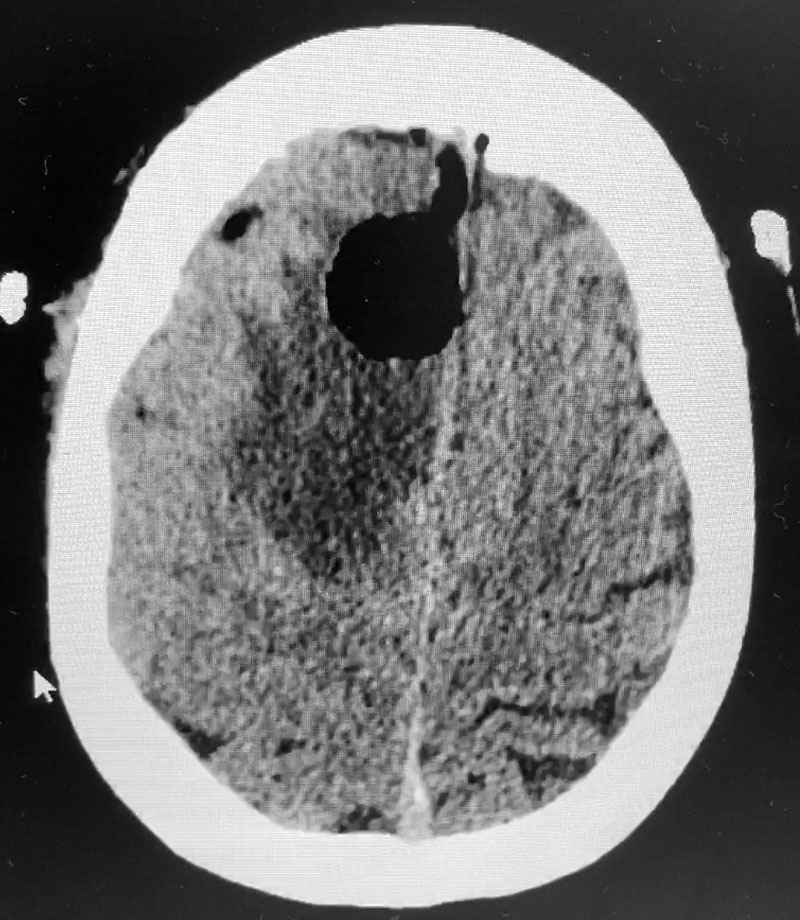

Figure 1: Sagittal post-contrast MRI.

The patient subsequently had increased headaches and weakness. MRI showed the mass had increased further, with persistent surrounding edema (Figure 1). Systemic work-up showed no active metastatic disease. It was suspected that there was recurrence of metastatic tumor as well as some component of necrosis (Figure 2). The patient underwent a right frontal craniotomy, by Dr. Michael Brisman, with brainlab stereotactic guidance. A cortical incision was made right over the mass. The mass was consistent primarily with metastatic tumor. The tumor was surgically removed.